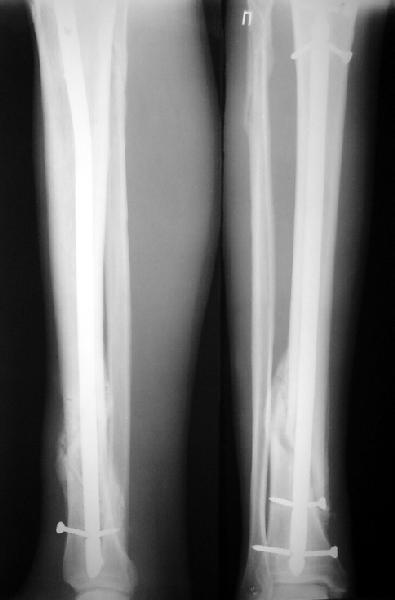

На мой взгляд, на снимках, приведённых Вами - неправильно сростающийся перелом дистальной трети большеберцовой кости, состояние после остеосинтеза интрамедуллярным гвоздём.

Как Вы пишите снимок под номером 1 - менсяц после операции, под номером 2- два месяца после операции.

Вы не послали послеоперационный снимок, поэтому трудно судить о состоянии редукции после операции.

Установка с медиальной стороны гвоздя в области дистального фрагмента дополнительного шурупа помогло бы Вам репонировать и удержать перелом в анатомическом положении, предотвратило варусную деформацию и смещение по ширине.

Пример, приведённый Вами в нашей дискуссии по времени нагрузки после остеосинтеза не совсем удачный... Ваш больной имеет счастье, что первым согнулся проксимальный замыкающий винт, а не дистальный и гвоздь не пенетрировал голеностопный сустав.